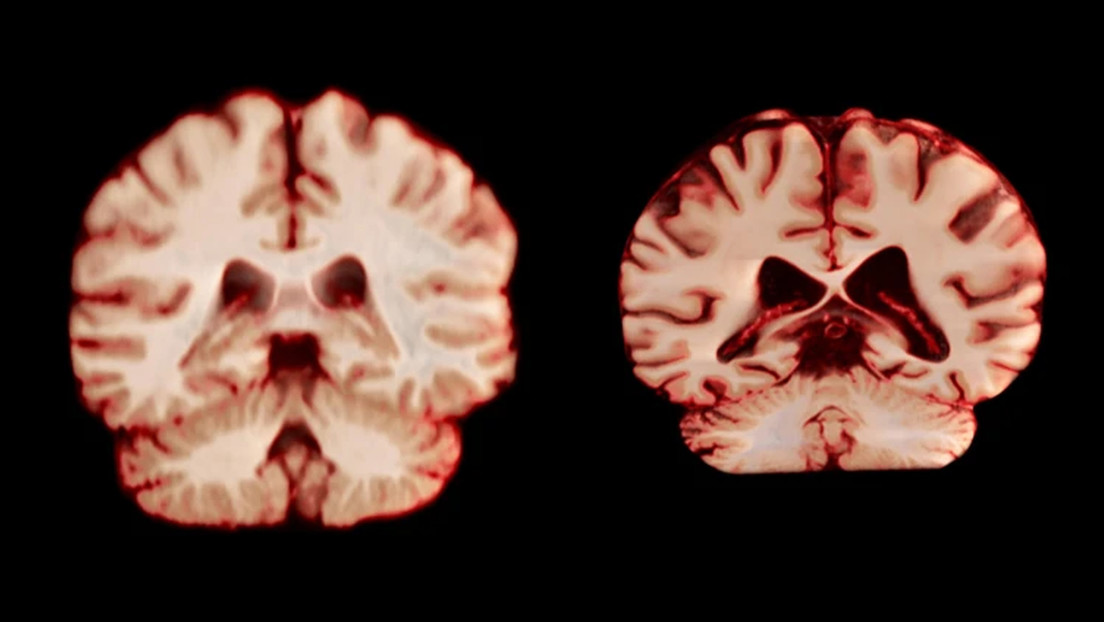

Atrofia del cerebro: ¿cómo recuperar el hábito de lectura, cuya pérdida causa este mal?

Revelan qué hace el alzhéimer mientras el cerebro descansa

Hacen retroceder el alzhéimer: logran que cerebros dañados recuperen la memoria en animales